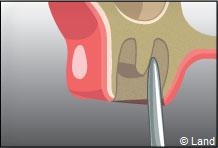

L’intervention commence là aussi par une anesthésie locale, puis le chirurgien-dentiste procède à une incision de la gencive et à un dégagement du tissu osseux autour de la dent.

Parfois cette dernière est sectionnée pour ne pas traumatiser l’os souvent responsable de suites opératoires douloureuses.